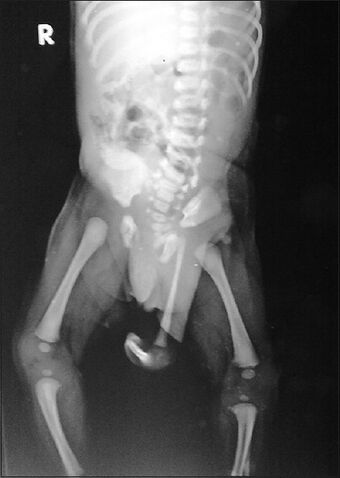

| Radiograph of a human child with polymelia |

Polymelia is a birth defect in which an affected individual has more than the usual number of limbs. It is a type of dysmelia. In humans and most land-dwelling vertebrates, this means having five or more limbs. The extra limb is most commonly shrunken and/or deformed. The term is from Greek πολυ- "many", μέλεα "limbs".